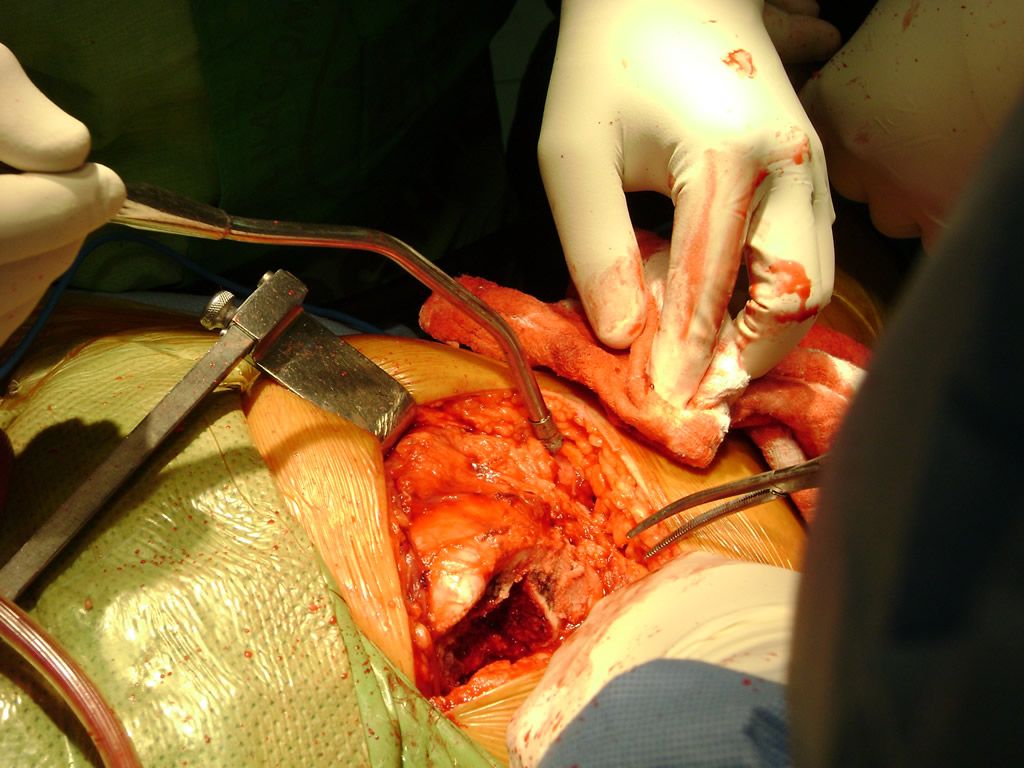

Cirugias en El Salvador - Perone y Tibia

Debido a la fina cobertura de piel que recubre la tibia y el peroné, las fracturas generalmente son abiertas, es decir, el hueso roto rasga la piel, atravesándola. Las fracturas de tibia y peroné generalmente se producen por un fuerte impacto o torsión.